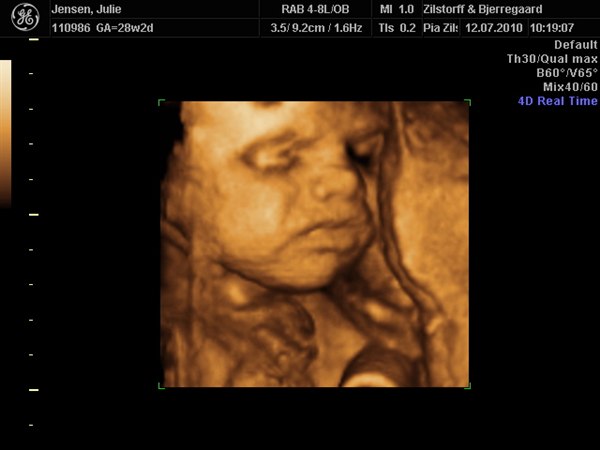

smilehuller og ligner helt sikkert Viktor

Kan slet ikke komme mig over hvor fantastisk det er at se det lille menneske inden i en

Vedhæftede fotos (klik for at se i fuld størrelse)